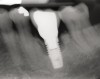

Clinical examination showed 2 mm of buccal recession with a shallow vestibule and absence of keratinized attached gingiva against the crown with 8 mm of circumferential pocketing accompanied by bleeding upon probing (Figure 15 and Figure 16). A periapical radiograph showed a symmetrical vertical osseous defect causing the loss of 50% of the bone around the implant (Figure 17). Because the patient had made a significant investment of time and finances to replace her lost tooth with the implant, she desired that the implant and restoration be retained, if feasible.

Fig 17. Radiograph showed symmetrical infrabony defect affecting 50% of the implant surface.